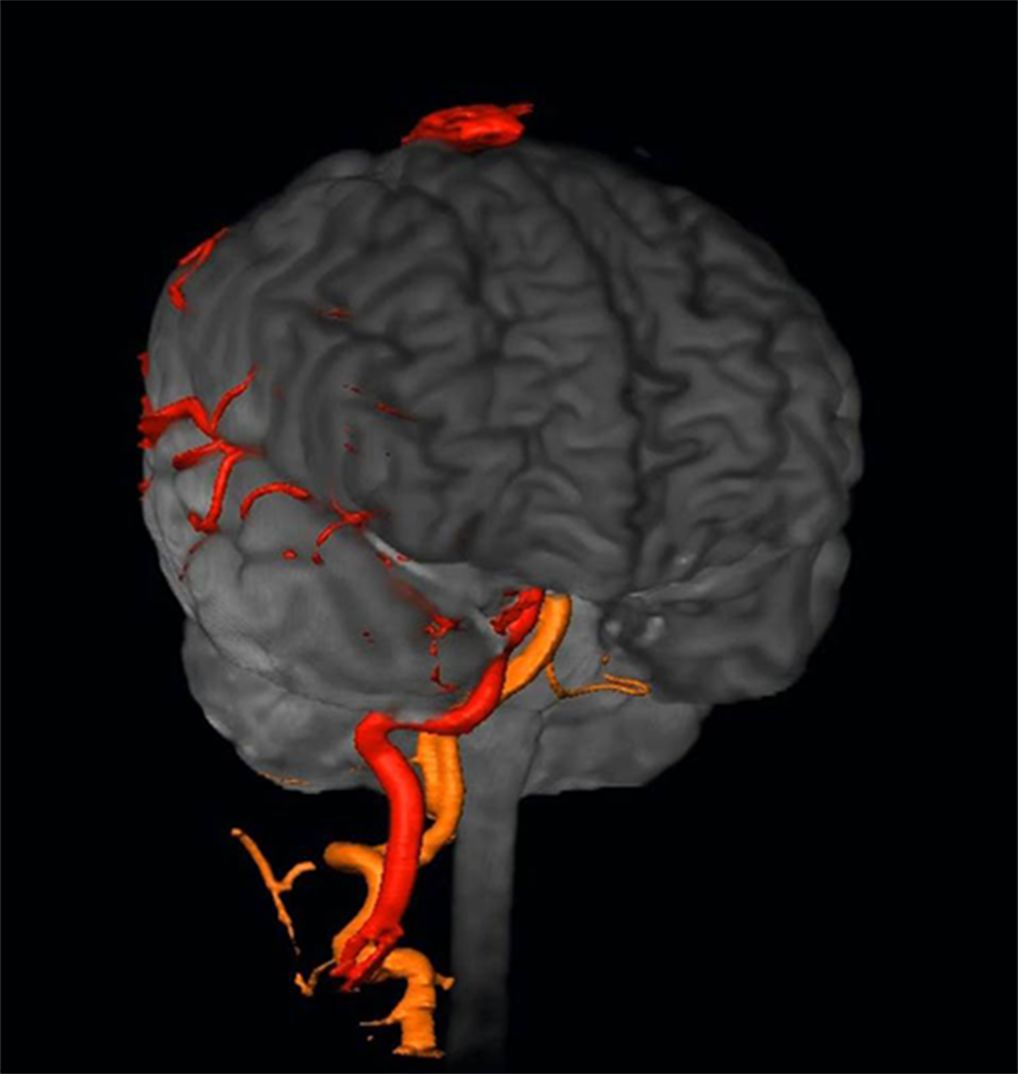

Neurosurgery10 脳動静脈奇形治療のこれまでとこれから 新到着 新NS 10】脳動静脈奇形治療のこれまでとこれから NOWの詳細情報

新到着 新NS 10】脳動静脈奇形治療のこれまでとこれから NOW。脳神経外科 専門治療 脳動静脈奇形|東京慈恵会医科大学附属柏病院。脳・脊髄動静脈奇形と頭蓋内・脊髄硬膜動静脈瘻。2017年発行の第1版です。【JMECC受講テキスト】内科救急診療指針2022【裁断済み】。脳神経領域:320列面検出器CTの最新画像がもたらす新たな展開。よろしくお願い致します。